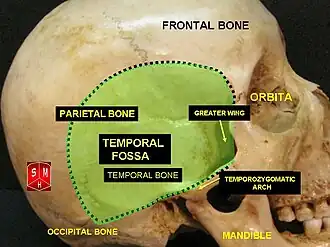

En el ser humano

La fosa temporal es claramente visible en esta imagen | ||

Fosa temporal | ||

La fosa temporal es una depresión poco profunda en el lado del cráneo delimitada por las líneas temporales y que termina por debajo del nivel del arco cigomático.

Límites

- Medial: Hueso frontal, Hueso parietal, Hueso temporal, Hueso esfenoides, Hueso occipital (huesos del neurocranium):

- Lateral: Fascia temporal

- Anterior: Superficie posterior del proceso frontal del hueso cigomático y la superficie posterior de la apófisis cigomática del hueso frontal.

- Superior: Líneas temporales (líneas temporales superior e inferior), que se arquean a través del cráneo de la apófisis cigomática del hueso frontal a la cresta supramastoidea del hueso temporal

- Inferior: Arco cigomático lateralmente y por la cresta infratemporal del ala mayor del esfenoides en sentido medial.

Contenido

- Músculo temporal

- Arterias temporales profundas

- Nervios temporales profundos

- Arteria temporal superficial (de la carótida externa)

- Nervio cigomaticotemporal